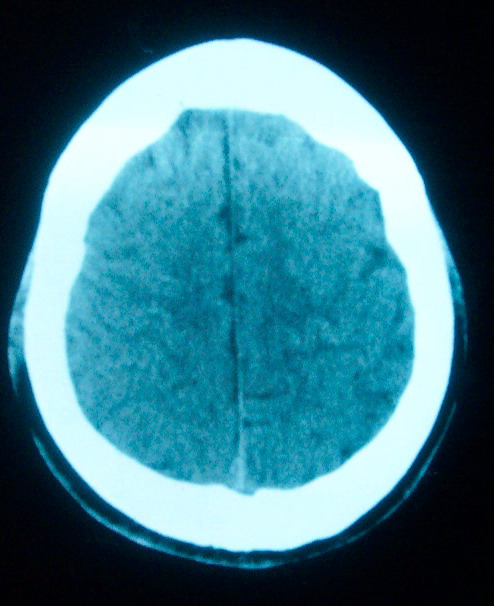

m     29    外伤1天   ct发现左额脑沟异常   请分析

我认为仅仅是左侧额叶脑回局部发育不良,脑沟与蛛网膜下腔略扩大而已没有巨脑回、硬膜下积液等情况。